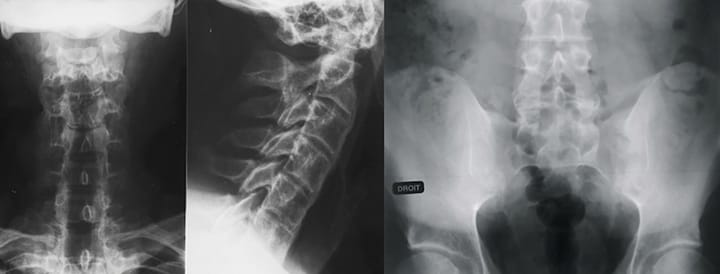

Rhumatologie Apport de la physiothérapie inductive dans la prise en charge d’un patient atteint de spondylarthrite ankylosante